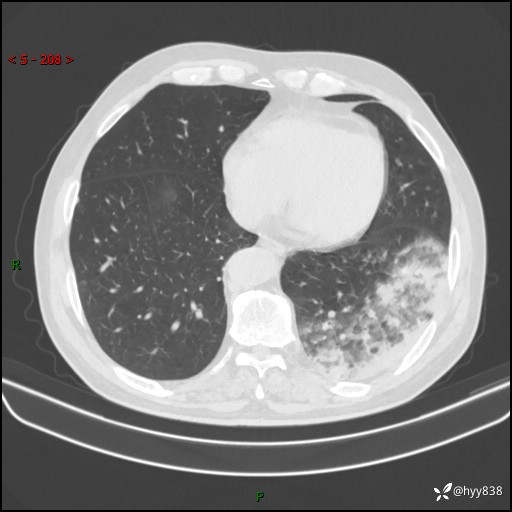

【患者信息】:59岁/男

【主诉】:发热伴咳嗽3天

【现病史及既往史】:患者3天前无明显诱因出现发热,体温最高达38.6℃,伴有咳嗽,干咳为主,感乏力、肌肉酸痛,无明显头晕头痛、鼻塞、流涕、呼吸困难、胸痛、恶心呕吐、腹痛腹泻、尿频尿急等不适,于当地诊所输液治疗3天感症状无好转,仍有间断发热、咳嗽,现为求进一步诊治,于我院门诊就诊,门诊以“发热待查”收入我科进一步诊治。 患者自发病以来,精神、饮食、睡眠欠佳,大小便正常,体力、体重无明显变化。

【检查】:胸部CT平扫